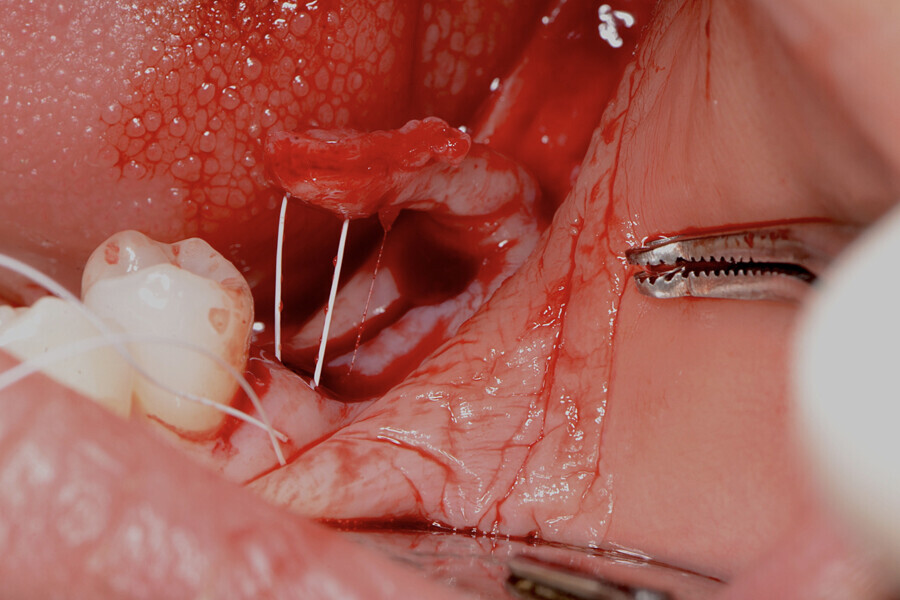

La papille mésiale a été préparée pour une greffe par une technique de tunnelisation (Fig. 10). Le lambeau obtenu a été suturé à la base du vestibule fraîchement créé du site receveur, au moyen d’un fil en PTFE non résorbable no 5/0 (Coreflon, IMPLACORE). Le greffon a été roulé à l’intérieur du rebord gingival et fixé en mésial, par des fils de sutures en PTFE (Figs. 11 à 14).

Le prolongement des incisions vers la région crestale et la distance qui les sépare, dépendent du volume de la greffe de tissu kératinisé nécessaire pour chaque cas. La désépithélialisation du lambeau a été effectuée à l’aide d’une lame n° 15C (Fig. 6), et un lambeau d’épaisseur partielle a été élevé (Fig. 7). Le lambeau a été décollé par une incision superficielle interne de la partie apicale, afin d’en permettre le déplacement passif et la suture sans tension. Le lambeau a alors été déplacé en direction mésiale avec une rotation de 180° (Figs. 8 et 9).